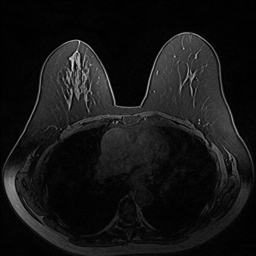

Magnetic field strength. 3T scanners offer higher magnetic field strength, improving signal-to-noise ratio (SNR) and image resolution for sharper, more detailed images [24]. However, they are more prone to artifacts, heating effects, and signal loss, especially around metal implants [5]. As such, our proposed dataset involving this spurious signal features a non-local spurious signal that influences the entire image rather than a localized region. An example set of images obtained from 1.5T and 3T devices are provided in Figure 3, showing that it is visually not possible to distinguish 1.5T MRIs from the 3T ones.